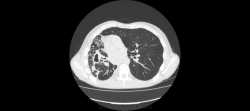

Здравствуйте, уважаемые коллеги! Меня зовут Владимир, работаю рентгенологом в ПТД, с недавнего времени осваиваю КТ. Хочу спросить вашего мнения по исследованию.

Больной наблюдается в ПТД с 2008го года. МБТ+ ни разу не было. На данный момент на фоне не специфической терапии отмечается снижение температуры, соэ остается высоким (60). Данные рентгенархива, к сожалению опубликовать не могу-нет фотоаппарата. Поэтому выкладываю сканы и видео.

Правое легкое уменьшено в объеме - значит есть фиброз, имеются полости распада - значит есть каверноз. А вот есть ли туберкуллез. Нет ВК, и локализация не вполне типична - в нижней доле. Может другой, столь же агрессивный возбудитель; например, актиномиккоз. Тема для консультации в вышестоящем ЛПУ.

Да, "неправильный" какой-то туберкулез. При таком массивном поражении одного легкого второе оказывается практически здоровым? Во всяком случае, своим неКТшным взглядом явной патологии не нашел. К тому же отсутствие ВК, и это при таких "кавернах"? Надо искать что-то другое, во всяком случае исключать. На вскидку даже трудно предложить дифряд. Что-нибудь грибково-простейшее?

Можно даже предположить, что первично был вариант или аномалия развития легкого, что-то связанное с врожденными кистами, гипоплазией и прочим.

Огромное спасибо за комментарии! Мне почему-то тоже пришла мысль о порочно развитом легком и присоединившейся позже инфекции, переросшей во временами обостряющийся хронический процесс.

Т.е. с Вашей точки зрения, процесс больше тянет на неспецифический?